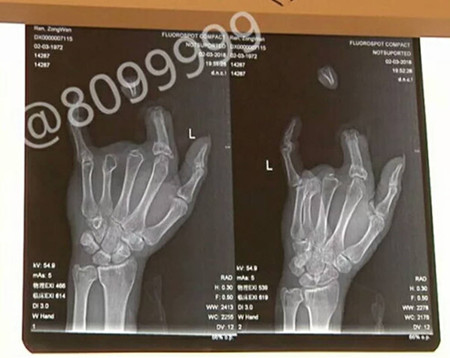

据了解,事发后,任师傅的妻子急忙收好丈夫的断指,又租了辆车把丈夫送到了昆明。在云南骨科医院,经过两个多小时手术,任师傅的断指被成功接好。目前手指循环良好,已经完全存活。

对于任师傅手指被缰绳勒断的原因,云南骨科医院手足显微外科王医生解释道:因为绳子受力面比较小,骡子力气比较大,这样就造成手指被勒在里面,用力一拉,手指的血管筋就全部被拉断。